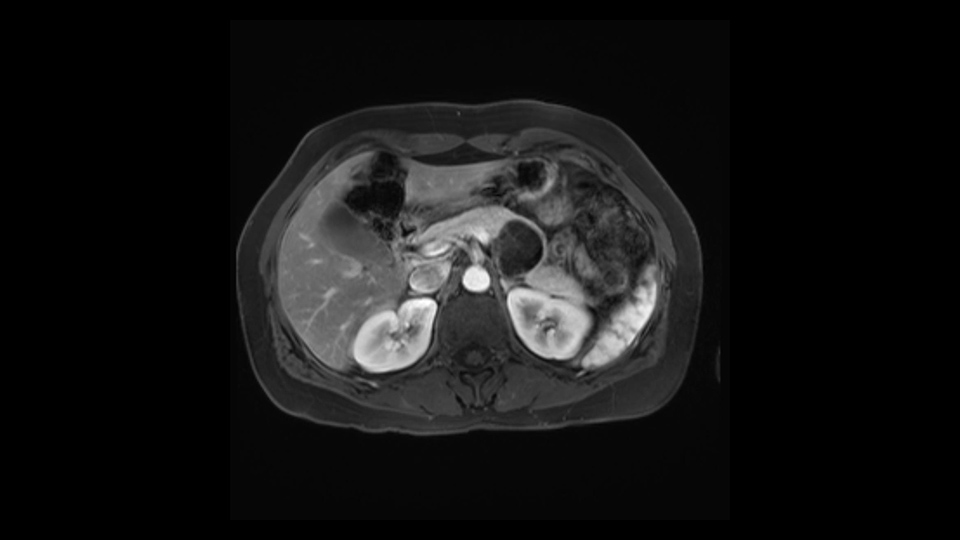

In reviewing this patient’s CT scan, first of all, the lesion is again cystic with a very thin wall. I anticipate that it will be delicate and potentially friable. And therefore the risk of rupture exists and we need to be very careful in how we handle the pancreas and the tumor throughout the procedure.

The lesion itself is quite adjacent to and abuts the splenic vein and therefore we need to anticipate that these two structures will be intimately related and possibly impossible to separate between the two.

The lesion also is quite posterior. While the plane between the cyst and the left adrenal gland is often preserved, we do have to pay attention here so that we remain in the right plane and maintain our margin here. Occasionally in these cases, en bloc adrenalectomy needs to be performed.

Hi my name is Carol-anne Moulton, I’m one of the surgeons here at TGH and an associate professor in the department of surgery. So I’ve had the ability to look at the MRI of this case that I’ve been asked to comment on. It has a mucinous or what appears to be a mucinous cystadenoma in the tail of the pancreas. To me, it looks like a pretty straightforward case. I agree with the decision to remove the tumor or cyst, give that it is unilocular and large and likely a mucinous cystadenoma. My preferred method of doing this particularly in a benign situation would be a laparoscopic distal pancreatectomy with or without the spleen.

The slowing down moments or considerations that I give when I look at the scan and plan my distal pancreatectomy is how far away the tumor is to the portal vein and do I have to formally create a tunnel behind the pancreas on top of the portal vein or do I have to take the pancreas further to the left of the portal vein or the patient’s left of the portal vein. So here I can see that here is the tumor here. I can see that the tumor is a fair way away to the patient’s right and so I will likely not have to take or create the tunnel formally in this procedure. And that speaks a lot to the resection margins. So its important when you’re doing a distal pancreatectomy or any procedure potentially for oncologic reasons to get clearance of the tumor and to take the tumor kind of intact.

The second slowing down moment or consideration I give to a distal pancreatectomy is the anatomy of the portal vein and the splenic artery. And so I look here and the anatomy is pretty straightforward. The splenic vein comes off normally and runs behind the pancreas and I can see the artery superior to that, again coming off in a normal manner from the celiac axis. So those two things, the portal vein and the splenic artery will be taken normally in this procedure.

The preoperative MR is very very important; any scan for that matter. Whether it is a pancreatic protocol CT scan or the MR as presented, the diagnostic imaging plays a very big role. And with this we see that it’s a very well-defined cystic focus in the body of the pancreas. Although there are septal enhancements, very well demarcated, but there is no vascular involvement. However, the mass appears to be in contact with the splenic vessel, and the mass is also a little bit in touch with the left adrenal and also the loop of bowel. So looking at this, basing on the features, I think it’s probably a mucinous cystic lesion, it could possibly be a pseudocyst. But basing on the history, it appears like there is no history that would point out to a pseudocyst. And not an IPMN as well; I don’t see any side branches from the MRCP and the MR scan and although there is no axial T2 images available, and I truly find it easier to identify the septations on T2, and the hepatic cyst that is visible on this scan makes it hard to differentiate it from a simple or complex cyst which may be considered in a mucinous neoplasm with cystic or mucinous metastasis. Basically the contrast would help us in identifying the enhancing mural nodules or septations in the cysts. The MRCP is definitely helpful to identify if there is any side branch, if we are considering any IPMN.

So first, I'll show you the scan. Here's the traditional view, where you see the cyst, which is in the body of the pancreas. And you see over here, it's got a quite thick wall. And going a little bit back also, here you see a septation which is very important, because I think a septation is what separates this from, for instance, the pseudocyst of the pancreatitis. And also the location of the cyst you see here, abutting the adrenal gland and going down a bit more, it's also quite close to a bowel loop. So when thinking about this cyst: female, the location in the body of the pancreas, thick wall, septation, and as you can read in history, it was basically asymptomatic, so no signs of pancreatitis. So, this probably all points towards a mucinous cystic neoplasm.